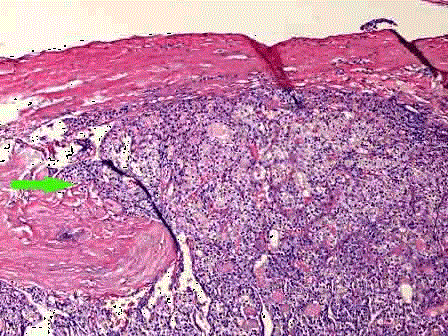

问题 图1为胃中低分化腺癌镜下观,图2为甲状腺滤泡癌镜下观,箭头所指表示了肿瘤的哪几种侵犯方式 ( )

选项 A.侵犯包膜 B.侵犯神经 C.侵犯脉管 D.侵犯表皮 E.以上都不是

答案 ABC